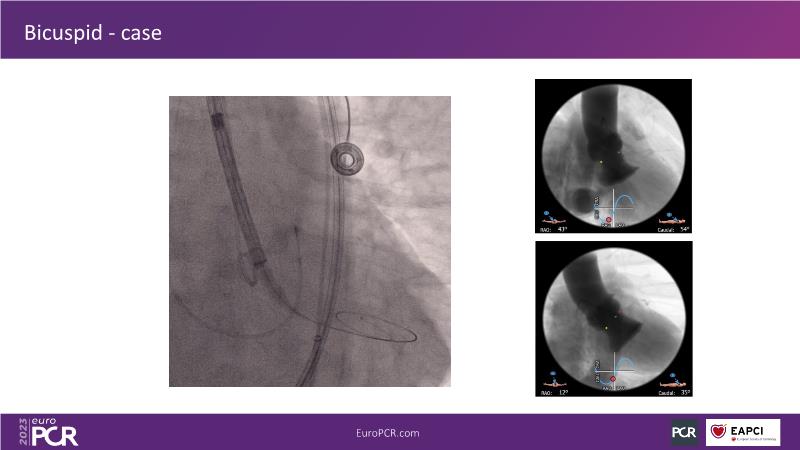

Discover the key factors to consider in selecting the optimal valve and implant technique for transcatheter aortic valve implantation (TAVI) to achieve optimal procedural outcomes. Gain insights into the impact of device choice and implantation technique on coronary access following TAVI and learn valuable strategies for tailoring your TAVI technique to complex scenarios, including bicuspid aortic valves, large and calcified anatomies, and ensuring coronary access.

- To learn how to tailor your TAVI technique to complex situations: bicuspid aortic valves, large, calcified anatomies and coronary access